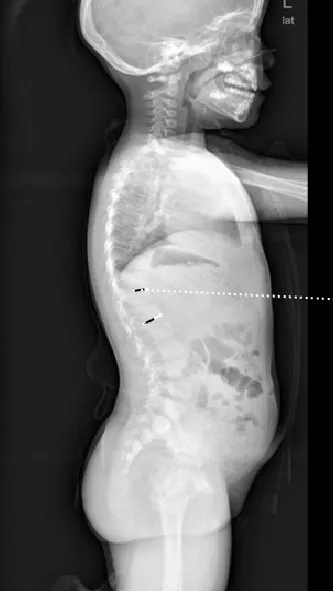

▷先天性脊柱畸形

先天性脊柱畸形,是指脊椎胚胎发育过程中,脊柱形成障碍或分节障碍所致的先天性脊柱畸形,包括侧凸、后凸和前凸,通常在婴幼儿期被发现。其中,半椎体畸形,尤其是完全分节的额半椎体,导致的脊柱侧凸保守治疗效果较差,早期诊断和手术治疗可避免严重的继发畸形,减少融合固定节段,保留更多的脊柱活动度,提高患儿生活质量。

▲ 女,7岁,先天性脊柱侧弯半椎体畸形